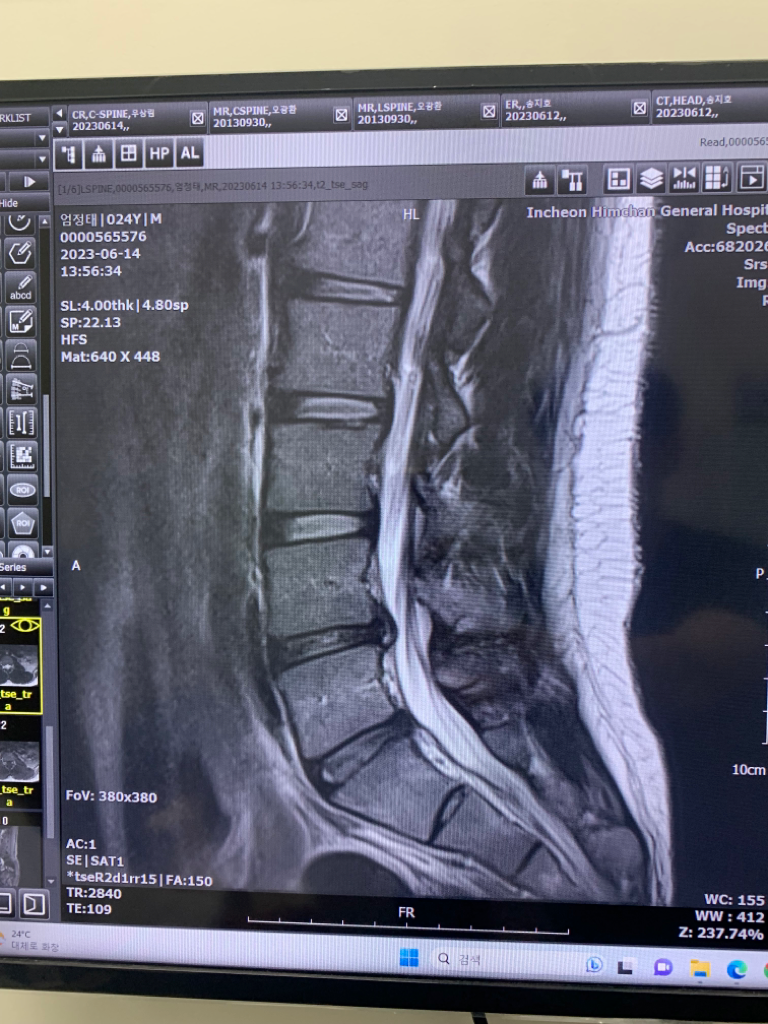

허리 디스크 섬유륜 파열 수핵 유출로 인한 손상후 해야할 것

안녕하세요 운동을 하다 뚝 소리와 함께 블랙아웃이 오고 mri 사진 결과 4번과 5번 사이의 디스크 섬유륜이 찢어져 수핵이 유출되어 신경을 찔렀다고 하는데 이게 맞는지 궁금하고 현재 척추가지신경 치료(block) 주사를 맞았는데 이게 신경 차단술인지 궁금하며,

• 1번 째 사진

현재 디스크 탈출로 신경이 눌리면서 증상이 나타나는 것으로 보입니다. 보존적 치료로 신경차단 주사 치료를 시행할수 있으며 ( 현재 시행하신 치료 ) 보존적 치료에 효과가 있다면 3-6개월정도 조심하면서 디스크가 흡수되는 것을 기대할수 있습니다. 만약 증상이 더 심해지거나 지속된다면 시술이나 수술적 치료도 고려할수 있습니다. 우선은 꾸준하게 치료를 받으시기 바랍니다.

네. 신경이 눌리고 있는 것이 확인되며 block이 곧 신경차단술이 맞습니다.

당분간 통증 조절이 신경쓰시고 무리한 움직임은 자제하셔야 하겠으며 통증이 호전되면 재활에 참여하시기 바랍니다.